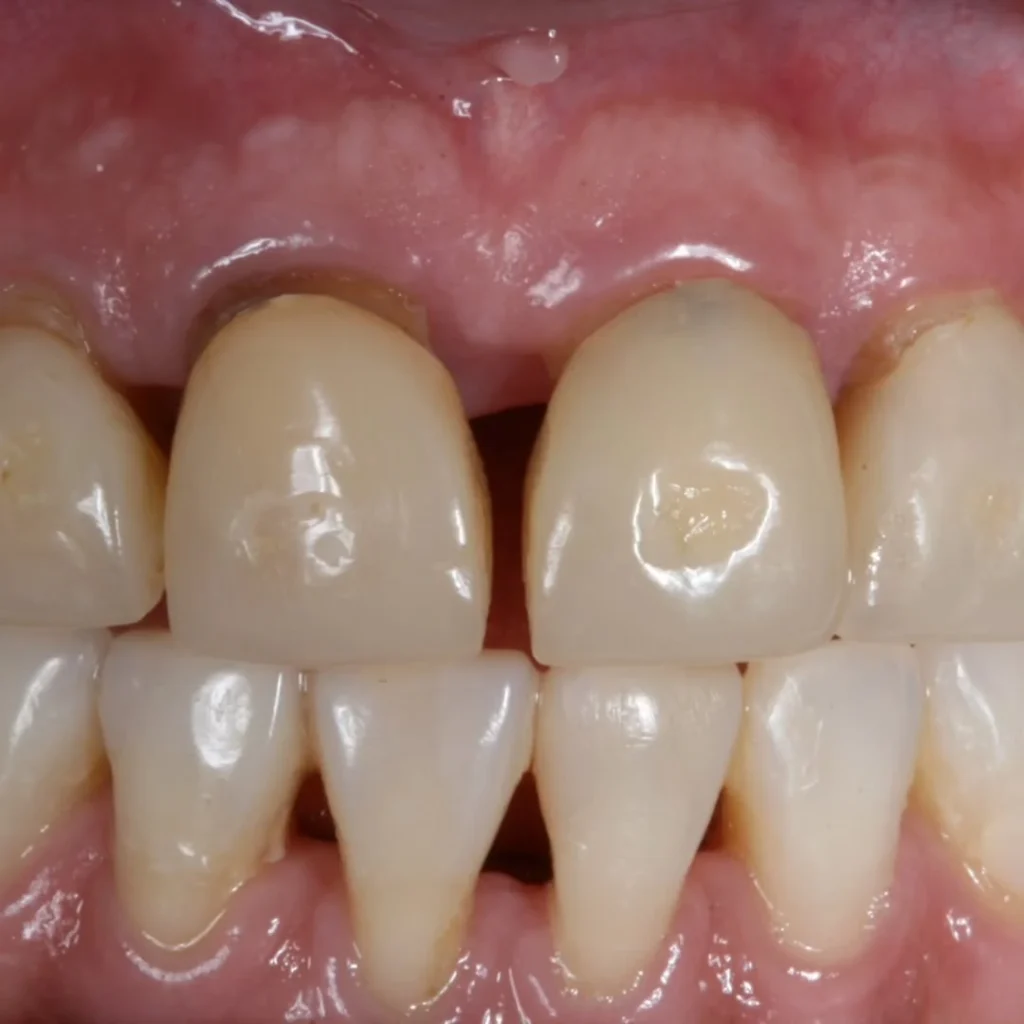

Mesmo após um tratamento ortodôntico bem executado, alguns pacientes apresentam espaços entre dentes anteriores, retração gengival e perda óssea. No caso apresentado, o incisivo central direito necessitou de implante com abordagem multidisciplinar para tratar a perda tissular e devolver harmonia ao sorriso.

Quando há retração gengival e perda de osso, apenas fechar os espaços não resolve. É preciso atuar sobre o biotipo gengival, espessura óssea e arquitetura do sorriso. Neste caso:

- Foi realizado enxerto gengival para recuperar contorno e volume;

- Houve necessidade de enxerto ósseo para estabilidade e suporte ao implante;

- As coroas foram desenhadas para mimetizar forma e anatomia naturais;

- A gengiva alcançou uniformidade e saúde visível no resultado final.